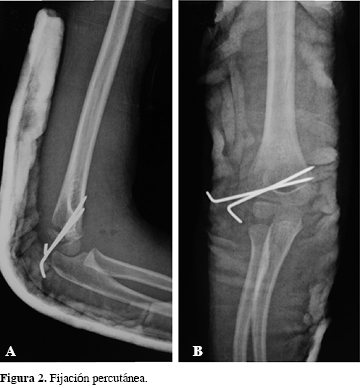

Se trata de una niña de cinco años de edad, previamente sana y sin antecedentes quirúrgicos ni traumáticos de ningún tipo, quien cayó desde una altura de 1.5 m, recibiendo un trauma directo en el miembro superior derecho con el codo en flexión y contusión por el cuerpo con posterior edema dolor y deformidad del codo derecho. Consultó al Servicio de Urgencias de nuestro hospital, presentando al ingreso edema en la región del codo derecho con equimosis localizada, deformidad y dolor sin déficit neurovascular distal. Se tomaron radiografías (Figura 1 A-C), donde se observó una luxación del codo derecho asociado con fractura del epicóndilo lateral. Consideramos realizar un manejo quirúrgico, con reducción cerrada fijación percutánea con clavos de Kirschner (Figura 2 A y B), llevada a cabo sin complicaciones (Figura 3). La paciente egresó con plan de fisioterapia y seguimiento con controles periódicos y al cabo de dos meses se encontró con resultados satisfactorios, con rangos de movilidad conservados con ligero cúbito en varo de 14 grados, el cual ha venido mejorando. Por todo lo anterior, consideramos que es un resultado postoperatorio satisfactorio con buenos resultados funcionales (Figuras 4 y 5).

El tratamiento de la fractura de epicóndilo lateral sin luxación del codo es controversial;3 en cuanto a los tipo I y II, algunos autores respaldan el manejo no quirúrgico.3 La mayoría de estudios coinciden que el manejo de la luxofractura debe realizarse precozmente, realizando reducción cerrada de la luxación y posteriormente una reducción abierta por abordaje lateral y osteosíntesis con dos o tres clavos de Kirschner, dependiendo de los hallazgos intraoperatorios.1,2,3,9,11 Algunos hallazgos intraquirúrgicos son la no lesión de la cápsula posterior y el ligamento colateral, pero sí la tracción de los músculos extensores en el fragmento epicondíleo, produciendo estabilidad por parte de las estructuras blandas a la luxación; si se produce una lesión posterior de la cápsula sí condiciona inestabilidad.1,8 La reducción de la fractura debe ser anatómica debido a esta relación de tejidos blandos con la estabilidad articular, ya que la reducción ineficaz puede llevar a incongruencia articular llevando a pobres resultados funcionales.1,2,3